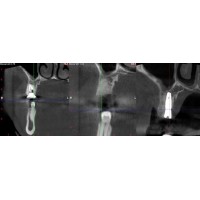

Розшифровка та вивчення КТ (

комп’ютерної томографії) верхньої та нижньої щелепи пацієнта. Знімок дозволяє

отримати точне тривимірне зображення щелеп. На його основі

стоматолог-імплантолог детальніше вивчає особливості щелепно-лицьового апарату,

кількість кісткової тканини і планує вживлення імпланта.